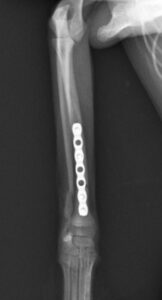

右前腕骨折のポメラニアンちゃんが来院されました。橈尺骨骨折は動物病院では一番よくある骨折です。ロッキングプレートであるTAITAN1.2で対応しました。治りも順調で元気に帰りました。よかったね。